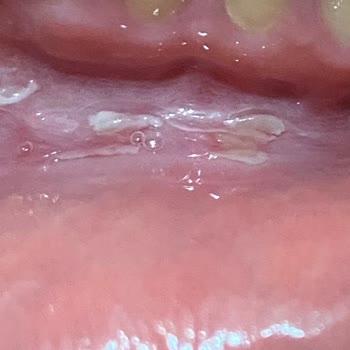

Parodontax Toothpaste Causes Painful Mouth Sores

After using the Parodontax toothpaste I bought for a few weeks, I observed the development of mouth sores, ulcers, and swelling on my tongue and cheeks. At first, I thought it might be due to stress or some other factor, but after coming across multiple complaints about the product, I came to the co...